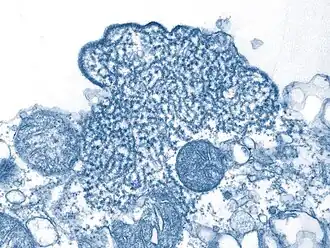

Вирус Нипах[3][4] (англ. Nipah henipavirus, ранее Nipah virus) — вид вирусов, вызывающий тяжёлую болезнь, для которой характерны воспаление мозга (энцефалит) или респираторные заболевания. Вирус Нипах тесно связан с вирусом Хендра (Hendra henipavirus) — оба вида принадлежат к роду Henipavirus из семейства парамиксовирусов (Paramyxoviridae). Природным носителем обоих вирусов являются плодоядные представители семейства крылановых (Pteropodidae).